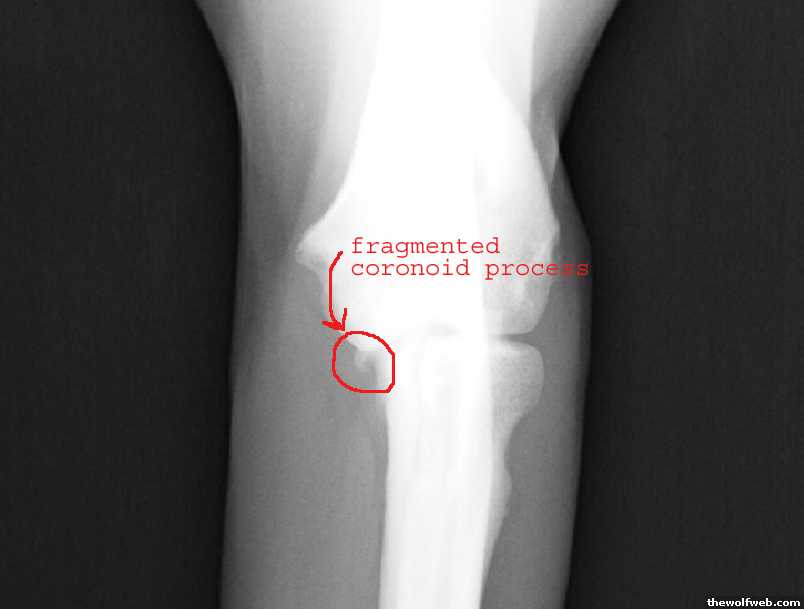

here are her xrays...

the fragmented piece, circled.

the typical arthritis caused by this broken piece